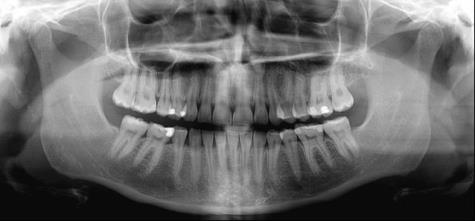

Koko leuan hammasröntgen on hammashoidon perustutkimus, joka kuuluu ottaa silloin, kun kuvantamiseen löytyy riittävä peruste. Hammaslääkärin kuuluu selvittää aina röntgenkuvauksen yhteydessä kuvauksen syy ja kertoa potilaalle, millainen kuvaus on riittävä suun tilanteen oikean diagnoosin saamiseksi.

Yleisimpiä kuvausvaihtoehtoja ovat pikkukuvat yksittäisistä hampaista tai koko leuan kuvantaminen. Näiden perusteella on mahdollista päättää, onko epäilyttäviä alueita tarvetta tarkentaa 3D-tomografiakuvauksella. Näiden kaikkien kuvausmenetelmien säteilyannokset ovat alhaisia.

Kuvantamisella voidaan selvittää yleisimmin ientulehduksen aiheuttamaa luukatoa, kariesta, hampaiden juurenkärkien alueiden tulehduksia ja viisaudenhampaiden tilanne. Koko leuan kuvasta hammaslääkäri näkee suun hoitohistoriaa. Näin saadaan tietoa hoidon suunnittelua varten.

Panoraamakuvat paljastavat yllättäviä löydöksiä

Hampaiston ja leukojen panoraamakuvausta selvittävässä väitöskirjatutkimuksessa hammaslääkäriä pyydettiin kirjaamaan jokaisen koko leuan hammaskuvauksen yhteyteen tarkka syy, miksi kuvaukseen päädyttiin. Selvisi, että lähes 70 prosenttia kuvista paljastaa suusta yllättäviä löydöksiä eli jotakin muuta, kuin miksi kuvaus on alun perin tehty.

Potilaalla voi olla särkyä ylhäällä vasemmalla, mutta koko leuan röntgenkuva paljastaa suun muilla alueilla olevaa kariesta. Tai jos suu kuvataan tietyn hampaan poistoa suunniteltaessa, tulehduksia löydetään aivan toiselta puolelta suuta. Hammaslääkäri joutuukin aina pohtimaan tapauskohtaisesti, onko potilaan edun mukaista ottaa koko leuan kuva yksittäisen hampaan sijaan.